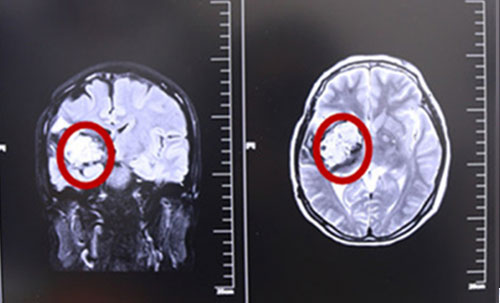

術(shù)前MRI影像資料,紅圈內(nèi)白色部分為腫瘤物

據(jù)核磁共振影像圖示,患者腦內(nèi)腫物靠近側(cè)裂動脈,并向大腦深部丘腦生長,且位于運動區(qū),已開始壓迫腦干。我院多位專家,包括政府特殊津貼專家侯增欣主任等為制定詳細(xì)的治療方案,展開了會診討論,鑒于患者張XX發(fā)作性面部抽搐、肢體無力伴頭暈等癥狀明顯,結(jié)合MRI影像資料,一致認(rèn)為顳頂海綿狀血管瘤診斷明確,有手術(shù)指征。